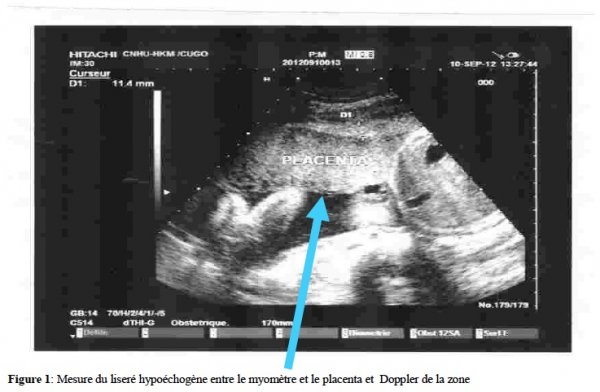

Il s’agissait d’une étude prospective et descriptive réalisée sur une période de 6 mois allant du 2 mai au 1er novembre 2012 et incluant 10 gestantes, sans autre pathologie associée, présentant un placenta bas inséré et ayant accouché à la CUGO. Les critères d’évaluation étaient : utérus cicatriciel, mesure du liseré hypoéchogène entre le myomètre et le placenta, doppler de la zone mesurant moins de 9,5 mm et lacunes intraplacentaires.

Il a été diagnostiqué un cas de placenta accreta. Il s’agissait de Mme Z.K. âgée de 42 ans, adressée au service d’échographie de la clinique universitaire de gynécologie obstétrique (CUGO) du CNHU-HKM de Cotonou pour une suspicion de placenta praevia. La gestante était 7ème geste, 2ème pare, aux antécédents d’une césarienne et de 4 fausses couches spontanées dont deux suivies de curetage. Le suivi de la grossesse en cause, a débuté après 07 semaines d’aménorrhées (SA). L’échographie au 1er trimestre, réalisée à 12 SA était normale. L’échographie morphologique au 2ème trimestre réalisée à 23SA et 5 jours à montré un placenta postérieur bas inséré type 2. L’échographie réalisée à 33SA a conclu à une insertion placentaire antérieure fundique avec un oligoamnios modéré . Compte tenu de la confusion sur la localisation placentaire, une échographie de contrôle à 36 SA a été réalisée, montrant un placenta postéro-latérale droit, recouvrant le col avec un liseré hypoéchogène entre le placenta et l’utérus, mesurant 5 mm sur une étendue mal définie (Fig. 1, 2), la vascularisation au doppler de la zone suspecte est sans signe vasculaire anormale. Un placenta accreta a été suspecté. Devant un score de Manning défaillant par un oligoamnios modéré, une hospitalisation a été préconisée pour une surveillance foeto-maternelle.